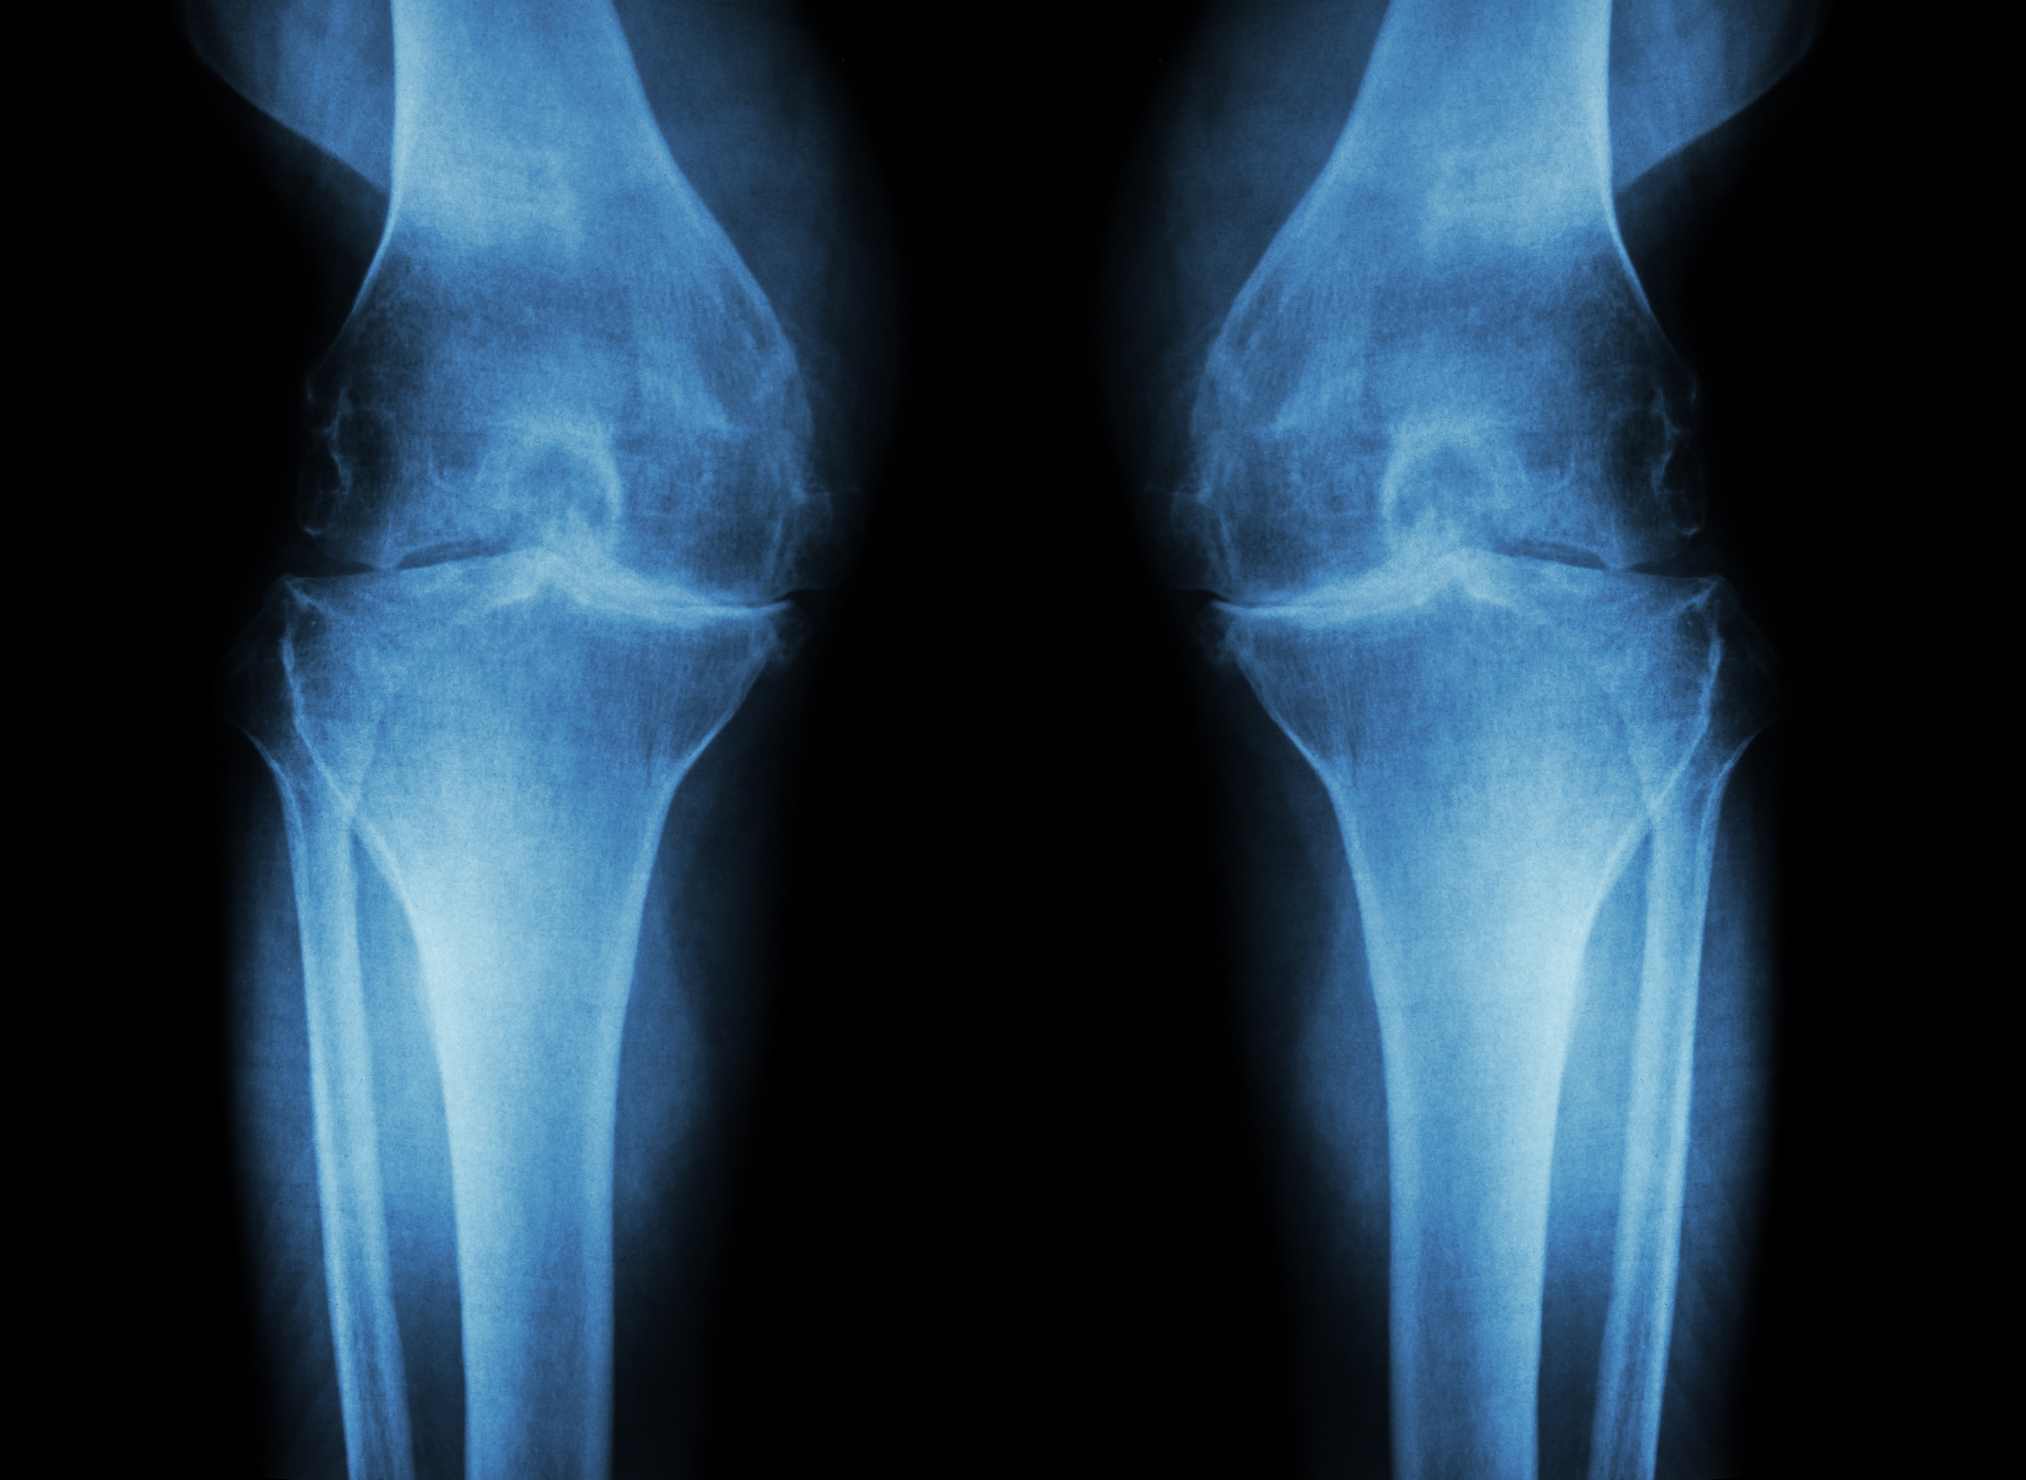

2. Bone-On-Bone Arthritis

A doctor will require x-rays to determine if the arthritis has progressed to the bone-on-bone stage. At this point, it is worth considering a knee replacement. For those with arthritis which shows only a deterioration of cartilage, it is probably not the best option. There are other treatment methods, and the arthroscopy may not result in a satisfactory replacement. When the bones are rubbing against each other, it causes extreme pain and damage.